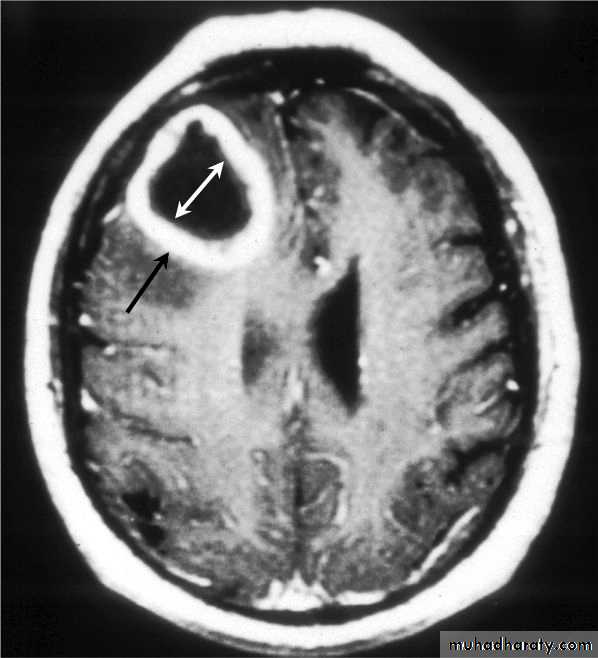

Brain Abscess MRI

Neurosurgery

• They will show a single (or multiple) space occupying lesion that is well delineated with an enhancing wall, with variable surrounding oedema.